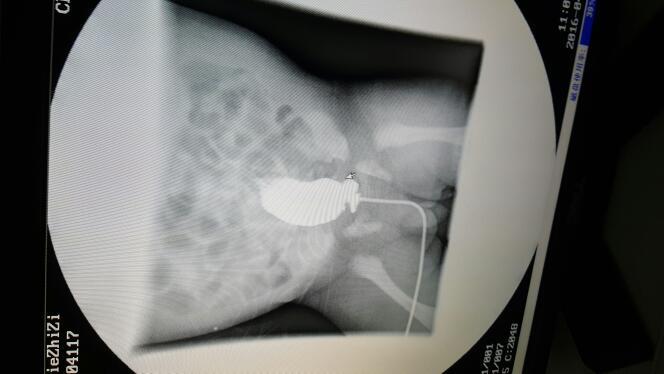

孩子出生后腹胀,大便不畅,住院六天后做造影,结果如下,医生说是巨结肠,需要手术,请问这种情况能保守治疗吗?如需手术大概什么时候做比较好?大概费用是多少?